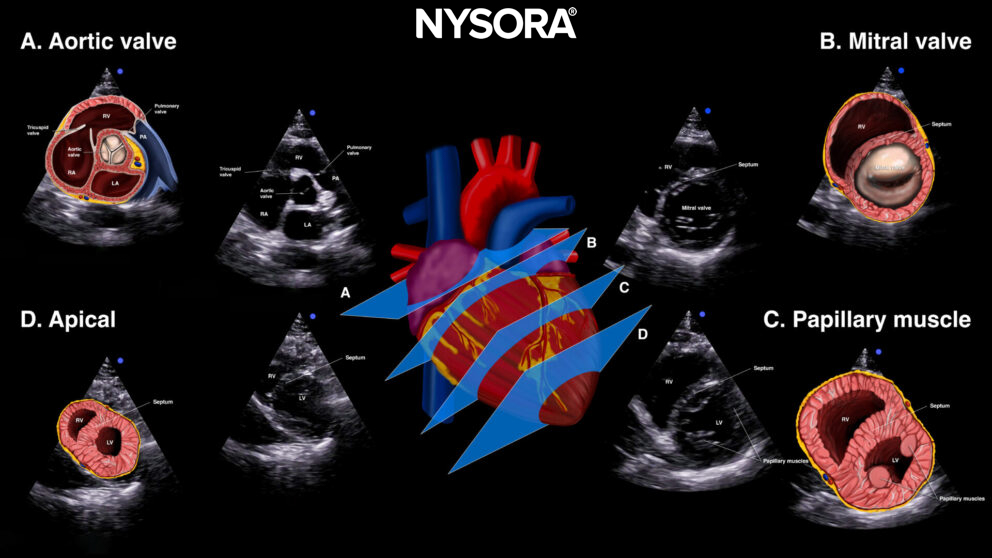

The standard parasternal short-axis view cuts the heart through the transverse plane.

Sonoanatomy of the heart in the parasternal short-axis view. Right ventricle (RV), septum, left ventricle (LV), and papillary muscles.

By tilting or sliding the transducer along the axis of the heart, other structures can be visualized next to the standard parasternal short-axis view. So in total, four levels of scanning can be obtained by tilting or sliding the transducer:

Tilting or sliding in the parasternal short-axis position provides 4 images: A. Aortic valve level (Mercedes-Benz view), B. Mitral valve level (fish mouth view), C. Papillary muscle level, D. Apical level.

A. Aortic valve level: ‘Mercedes Benz’ view: This is a good view to assess the aortic valve, the right ventricle, the tricuspid valve, and the pulmonary valve.

B. Mitral valve level: ‘Fish mouth’ view: Right ventricle and mitral valve.

C. Papillary muscle level or standard parasternal short-axis view: Right ventricle, left ventricle, papillary muscles (posteromedial and anterolateral papillary muscle).

D. Apical level: Here, the papillary muscles are gon,e and it is possible to assess the apex.

Practical use:

- Left ventricular function

- Right ventricle dilatation: a D-shaped right ventricle represents pressure and volume overload (See “Clinical applications)

- Pericardial effusion

- Valve function:

- Aortic valve: ‘Mercedes Benz’ view

- Mitral valve: ‘Fish mouth’ view: anterior and posterior leaflet

- Volume status: kissing left ventricle papillary muscles at the end of the systole indicate hypovolemia